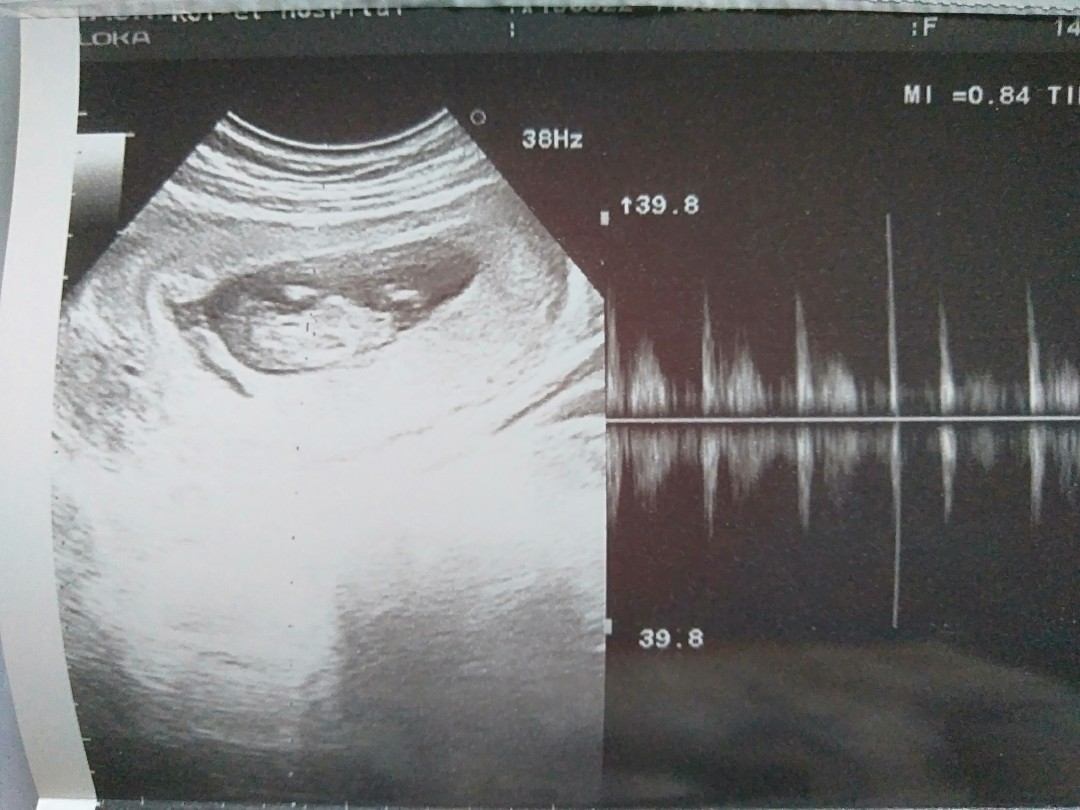

14w1d

Post reply image